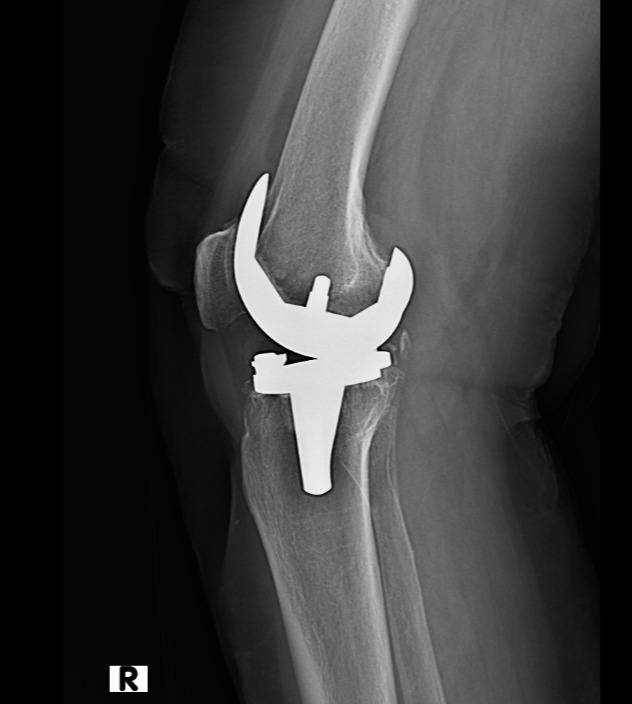

Eklem protez cerrahisi (artroplasti), halk arasında “eklem protezi” olarak bilinir. En çok kireçlenen eklem ve en çok protez uygulanan eklem diz eklemidir. Bunun ardından Kalça eklemi gelir. Ayrıca omuz, ayak bileği ve el bileği eklemlerinde de kireçlenme yani artroz sonrası eklem protez cerrahisi uygulanmaktadır. Eklemlerimiz zamanla yıpranabilir veya kireçlenme nedeniyle görevini yapamaz hale gelebilir. Bunun birçok sebebi vardır. Bu durumda protez cerrahisi sayesinde ağrısız hareket etmek, günlük hayata geri dönmek mümkündür. Türkiye'de protez cerrahisi 90'lı yıllarda İstanbul, İzmir ve Ankara gibi illerde yapılırken şu an her şehirde yapılabilmektedir. Ege Üniversitesi'nde diz protezi ve kalça protezleri konusunda 40 yıllık deneyimi olan Hakkı Sur ile eğitim aldıktan sonra Fransa'da yine ünlü protez merkezinde birçok vakaya katılmış ve yapmış olmanın bu cerrahideki önemini meslek hayatımda daha da idrak ettim.

Klinik uygulamada protez olan hasta ameliyat sonrası ilk günde ayağa kaldırılmaktadır. Yatak içi ve yatak kenarında fizik tedavi hareketleri yapılmaktadır. 2. gün hastanın hareket açıklığı artırılmaktadır. 3. günde ise fizyoterapistler eşliğinde merdiven inip çıkma egzersizleri öğretilmektedir. Hasta evine giderken sondası çıkmış ve tuvalete gidebilecek şekilde plan yapmaktayız. Dikişler için 15 gün sonra kontrole gelen hasta tekrar değerlendirilmektedir.